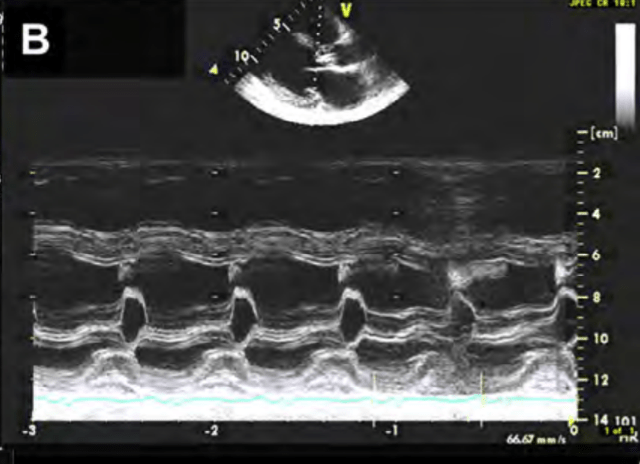

M-mode tracing shows this specific valvular abnormality

What is acute aortic regurgitation?